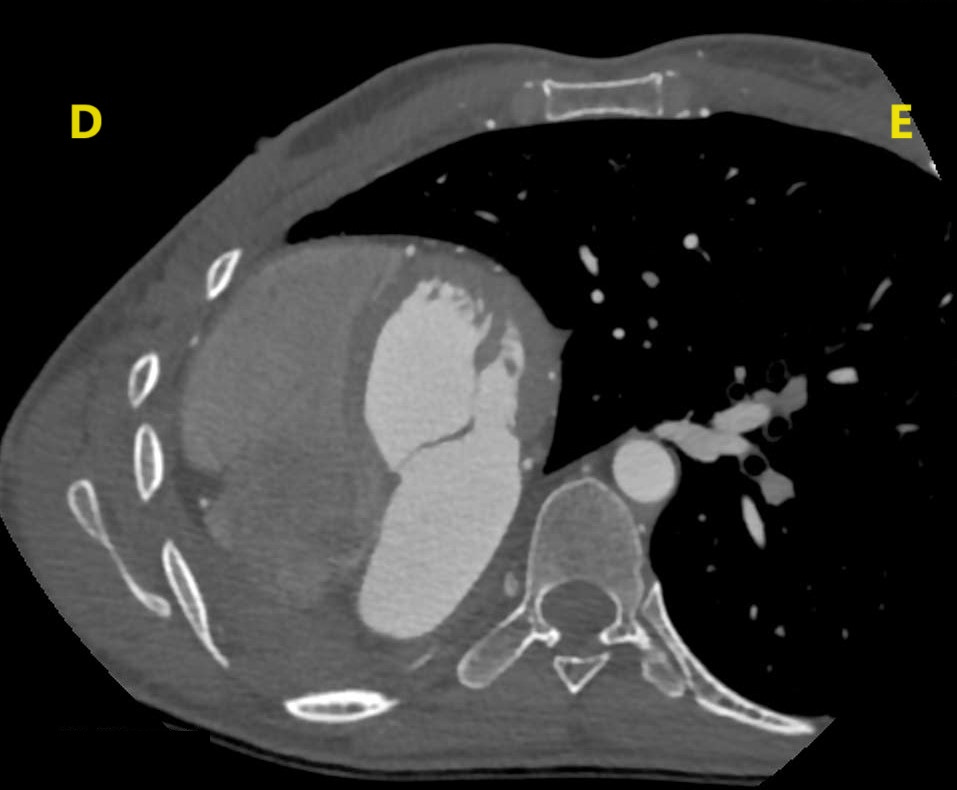

Imagem da Semana

I want to play a game (Jigsaw).

Essa é uma angiotomografia de paciente 37 anos. Queremos saber:

Na próxima semana trazemos a resposta!